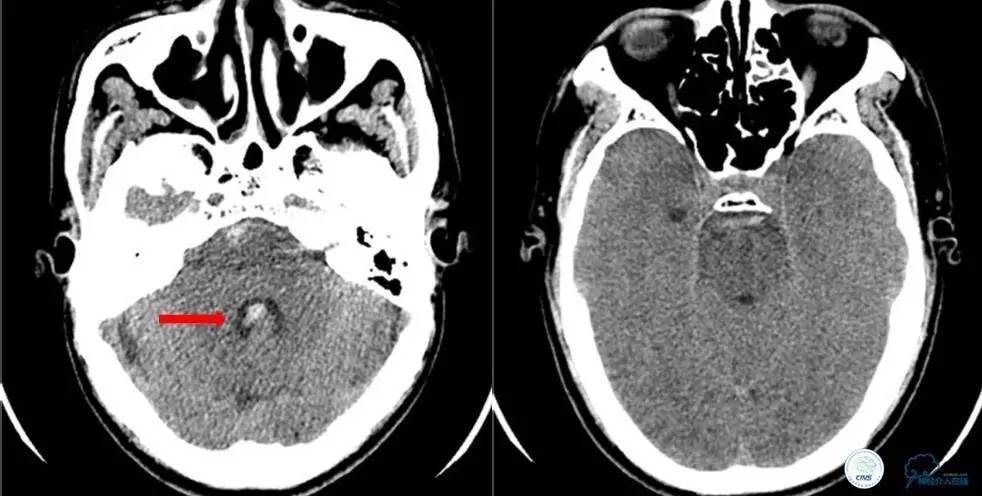

小陈,男,38岁,因突发头痛3天到医院就诊。入院前3天在颈椎按摩过程中突发头痛,呈全头部闷胀痛,伴头晕,一过性双眼黑矇。既往高血压病史1年。入院查体言语清晰,双眼球各向运动到位。示齿鼻唇沟对称。四肢肌力5级。双侧病理征阴性。颈抵抗,颏胸距4横指,克氏征阳性,布氏征阴性。余未见异常。入院后查了头颅CT,提示蛛网膜下腔出血。

入院时颅脑CT